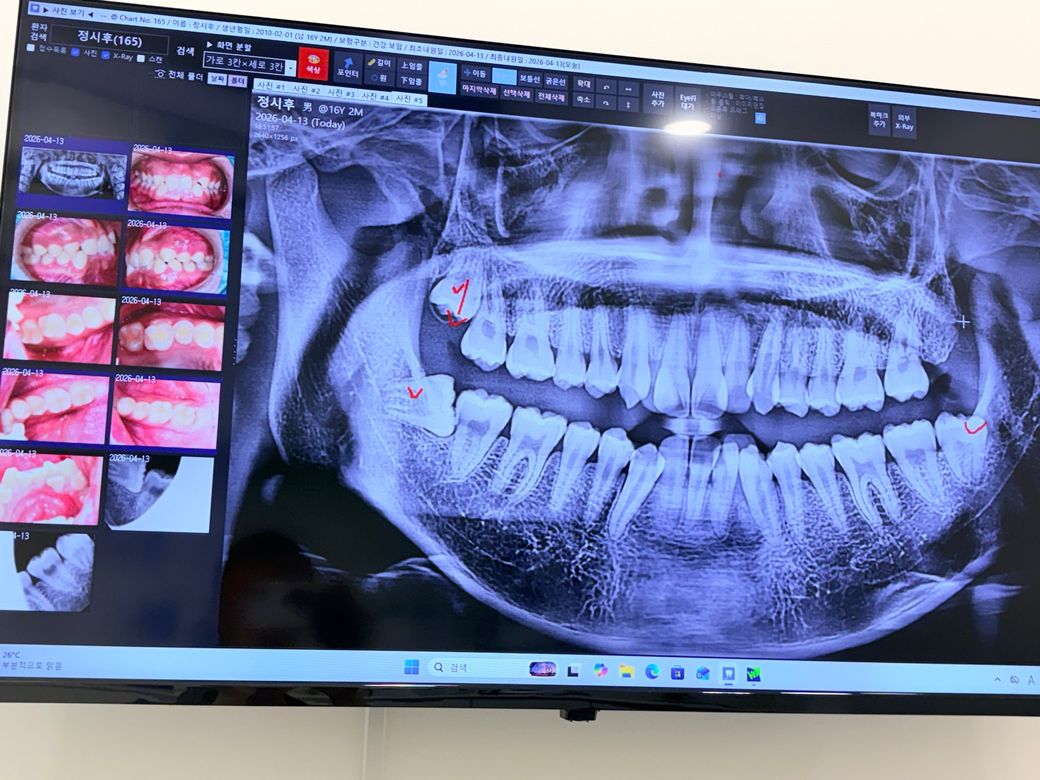

안녕하세요 학교 건강검진중 충치가 있다고 하여 치과에 가보게되었습니다 치과에서 X-ray 를 찍었는데 사랑니가 3개가 있고 그중 아랫니2개를 뽑아야한다고 하셧습니다

이거 빼야할까요?

• 1번 째 사진

당장 빼야한다 그런건 아니지만 부분매복 사랑니는 앞으로 옆 치아에 대해 치근흡수, 충치 유발 내지는 잇몸염증을 유발할 확률이 있기 때문에 빼주는게 좋긴합니다